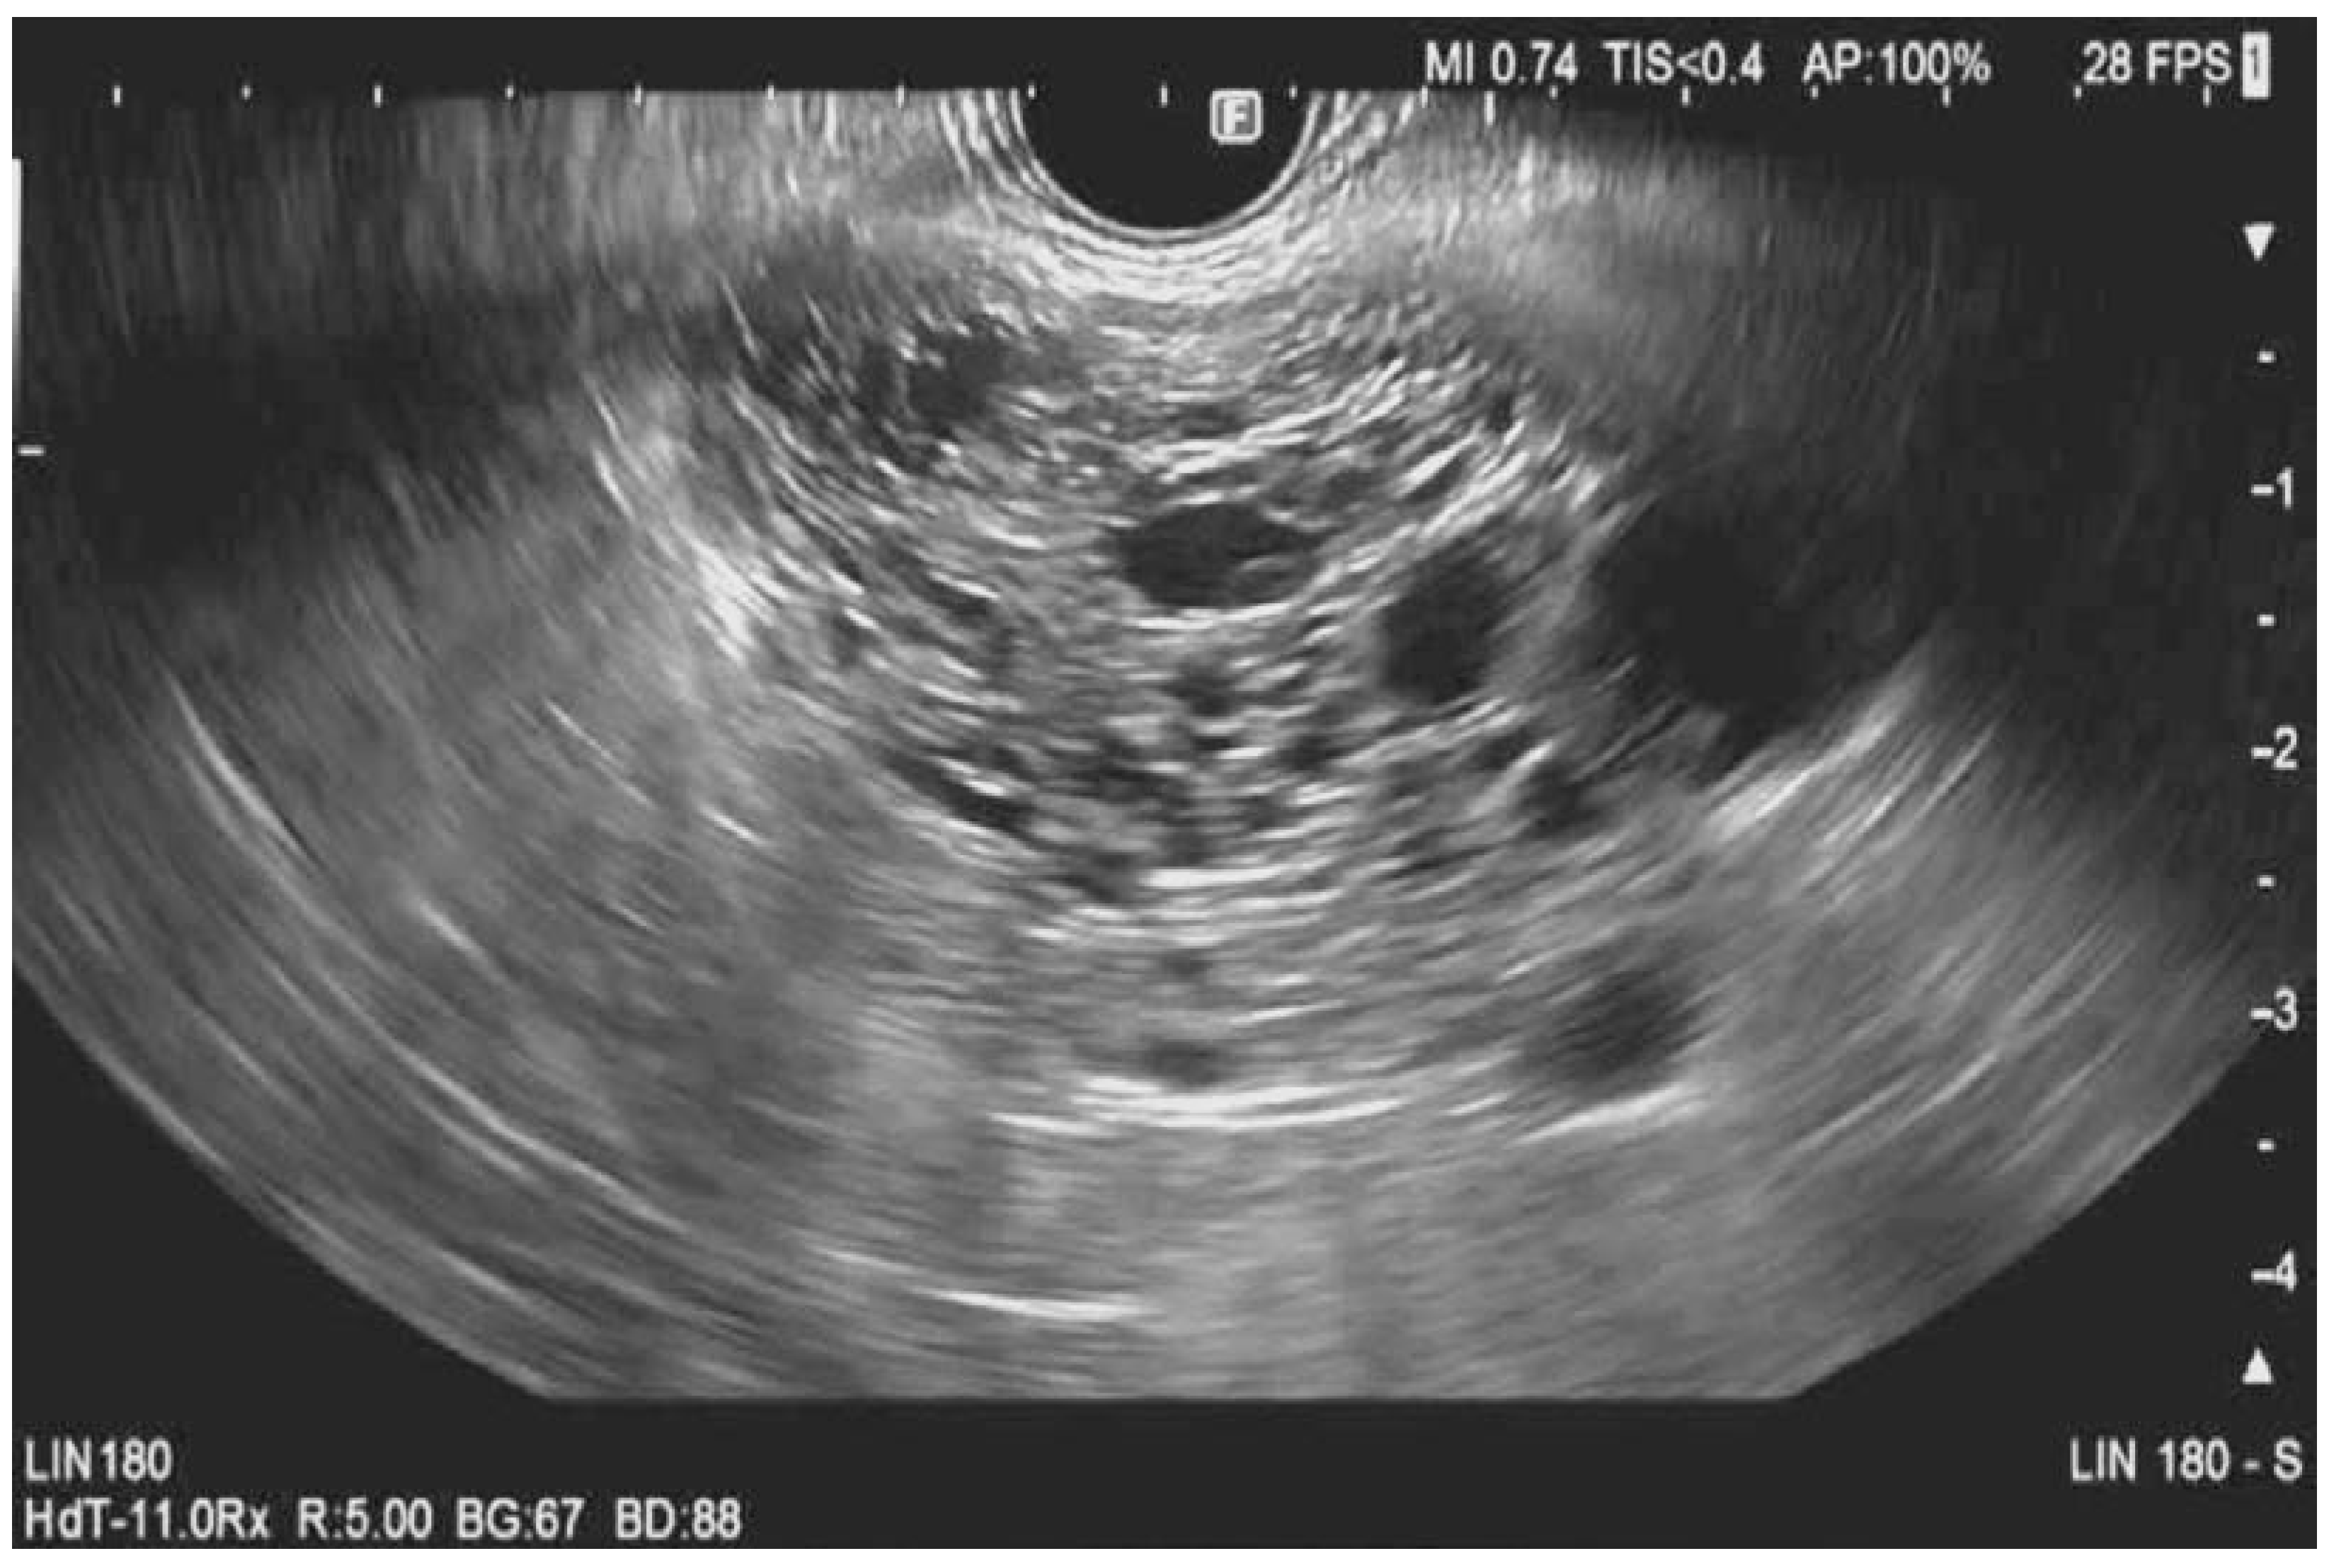

Contrast-Harmonic Mode Endoscopic Ultrasound